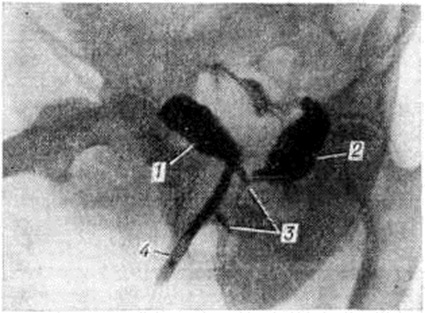

Сложные и комбинированные свищи. Весьма тяжёлое клиническое течение характерно для сложных и комбинированных свищей, при которых одновременно существует патологический сообщение между мочевым пузырём, влагалищем и прямой кишкой (рисунок 3) или имеет место значительное разрушение дна, мочепузырного треугольника и боковых стенок мочевого пузыря с полным или частичным дефектом задней стенки уретры, что приводит иногда к искусственной влагалищной экстрофии (выпадению) мочевого пузыря. У таких больных моча содержит примесь газа и кала, развиваются воспалительные осложнения со стороны мочевого пузыря и почек. Постоянное подтекание мочи из влагалища ведёт к мацерации промежности и бёдер с развитием гнойничковых заболеваний кожи. Больные избегают общества, у них часто наблюдается тяжёлое депрессивное состояние.

Консервативное лечение сложных Мочеполовые свищи, как правило, не приводит к выздоровлению и может только уменьшить воспалительные осложнения. Оперативное лечение часто многоэтапное с использованием в качестве пластического материала сальника, стенки мочевого пузыря, матки и кожи; оно даёт высокий процент рецидивов. Повторные вмешательства приводят к формированию массивных рубцов, значительному уменьшению ёмкости мочевого пузыря, к деформации кишки и влагалища; утрачивается способность тканей к регенерации, что делает невозможным ликвидацию свища и восстановление физиологический функций. В подобных ситуациях производят операцию кольпоклейзиса (сшивание стенок влагалища ниже свища) или эпизиоклейзиса (зашивание входа во влагалище), что позволяет создать мочевой резервуар с трансректальным мочеиспусканием.

При сложных неоперабельных свищах со значительной дилатацией мочеточников осуществляют отведение мочи посредством уретерокутанеостомии (смотри полный свод знаний Уретеропластика) или двусторонней нефростомии (СМ.).